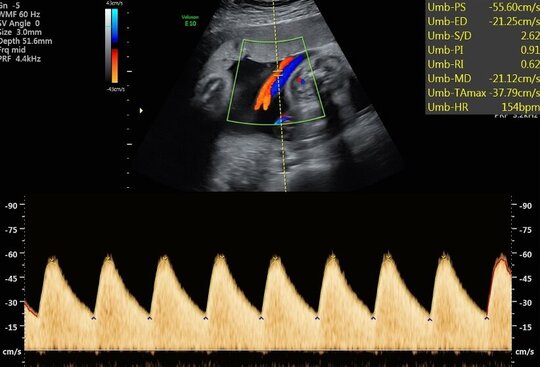

Ultraschalluntersuchung der mütterlichen und kindlichen Durchblutung (Farb-Dopplersonografie)

Die Durchblutung der Nabelschnur, der kindlichen Gefäße und des Mutterkuchens wird mittels einer speziellen Ultraschalltechnik durchgeführt. Mit der sogenannten (Farb-)Dopplersonografie können wir in der Pränataldiagnostik und Schwangerenambulanz die Versorgungslage überprüfen.

Auffällige Blutflussmuster können auf eine Mangelversorgung des Ungeborenen oder Auffälligkeiten im Kreislauf der Mutter hinweisen. Zu nennen wäre hier das erhöhte Risiko für einen schwangerschaftsbedingten Bluthochdruck. Mittels der Untersuchung können solche Probleme rechtzeitig erkannt und die Patientin entsprechend am UKS überwacht werden.

Nabelschnurarterie